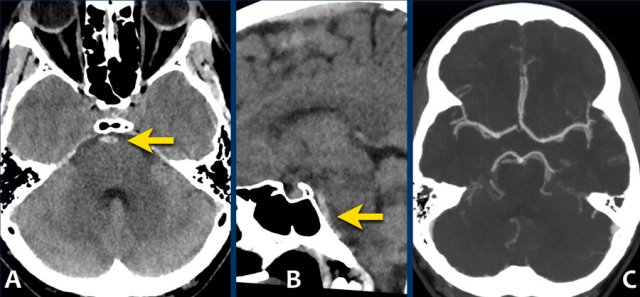

The images show a slightly hyperdense focus in the prepontine and interpedunclair cystern in a patient who presented with acute severe headache.

DSA did not show an aneurysm.

This patient complained of sudden onset headache with the sensation of a “burst” inside his head.

Neurological exam was normal, except for a stiff neck.

The NECT showed a small amount of subarachnoidal blood anterior of the brainstem.

CTA showed no abnormalities.

DSA was not performed.

Here another example of a nonaneurysmal perimesencephalic SAH.

Left image: NECT showed a small amount of subarachnoidal blood anterior to the brainstem.

Right image: more cranially, the pentagon, ambiens cistern and the proximal part of Sylvian’s fissures, did not show any blood.

This is a typical presentation of nonaneurysmal perimesencephalic SAH.

The blood is solely located around the brainstem.